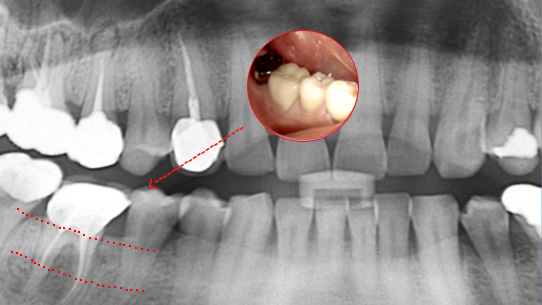

심한 염증으로 치조골이 광범위하게 소실, 아래쪽 신경관이 가까이 있어 치근단수술이 불가능한 상태, 타 병원에서 임플란트 진단을 받았지만, 고운미소치과에서 치아를 발치하고 뿌리 쪽 염증을 제거한 후 발치한 치아를 다시 심는 치아재식술을 시행하였습니다.

기존 신경치료 부위에 염증과 치조골이 소실되고 있는 상태

치아를 발치하고 염증을 제거, MTA로 충전하고

치아를 다시 심음. (난이도 중)